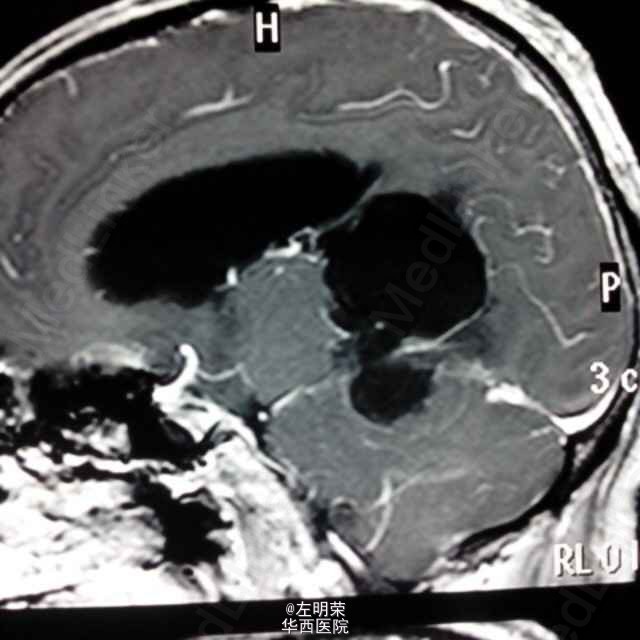

中年男性患者,“反复头痛一年”入院。查体未见明显异常;头部MRI示:松果体区占位,梗阻性脑积水。术中见病变位于右侧脑室三角区,病变范围广泛,侵及丘脑,脑干背侧,松果体区,呈白色珍珠状,质脆,切除过程中出血少,有白色坚韧包膜,予以全切,患者术后恢复良好;病理结果:松果体区表皮样囊肿。